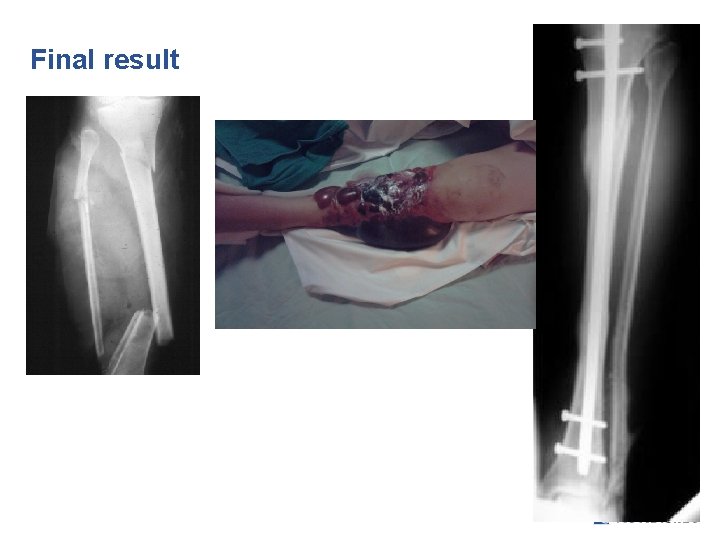

Final result

16 -year-old male fell from 10 m • Open wound • Distal neurovascular status is normal • Irrigated and debrided

Your treatment of choice? 1. IM nailing 2. Plate 3. External/ring fixation 4. Temporary fixation with external fixation, then definitive treatment 5. Cast

Definitive treatment?